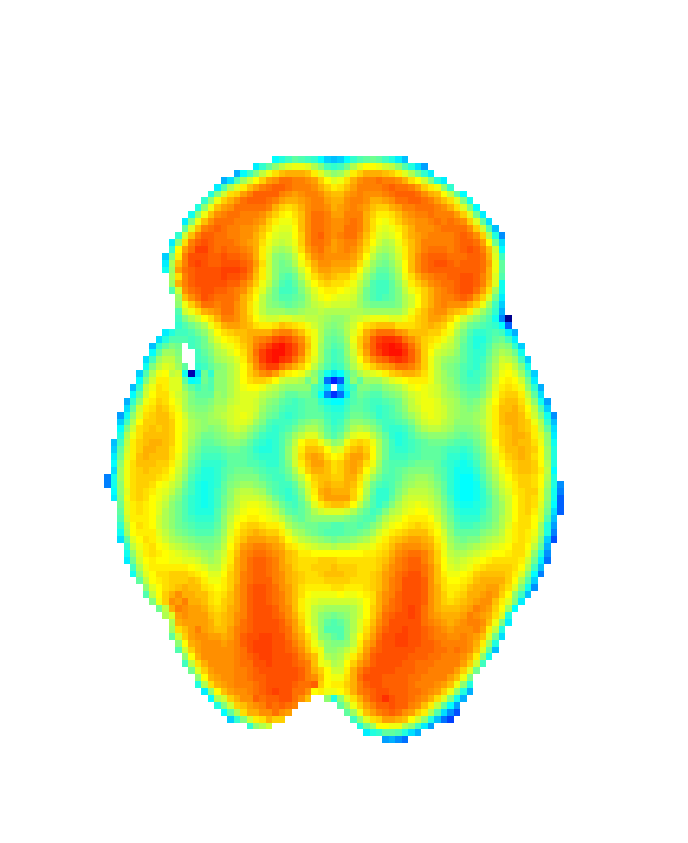

In order to obtain 18F-FDG PET data we drawn upon the Alzheimer’s Disease Neuroimaging Initiative (ADNI) [56], a platform that collects data from different research institutions focusing on AD diagnosis. We selected 18F-FDG PET and MRI data, together with demographic information (age and sex) for CN group (75 patients; 44 male; age: 75.56±4.96plus-or-minus75.564.9675.56\pm 4.96 years) and AD group (51 patients; 30 male; age: 74.03±7.25plus-or-minus74.037.2574.03\pm 7.25 years) summing 126 participants. Images were then realigned, unwrapped, co-registered with MRI data, spatially normalised, mean proportionally scaled, and masked following standard procedures deployed by SPM with the aim of guaranteeing voxel-to-voxel comparability between images (see Figure 2).

Refer to caption

(a) Raw image

(b) Normalized image

(c) Masked image

Figure 2: Stages of 18F-FDG PET processing. (a) Raw image obtained from ADNI, (b) image after anatomical standardization, (c) processed image after masking.